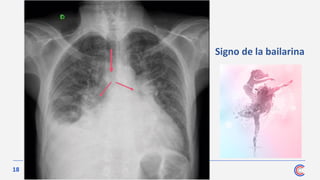

Lo más caracterís tico es el crecimiento de la aurícula

Radiografía de tórax

Las demás cavidades cardiacas no aparecen dilatadas en la estenosis mitral

pura, a menos que se desarrollen hipertensión pulmonar arterial significativa y fallo

derecho, que producirá CARDIOMEGALIA a expensas de las cavidades derechas y de

la arteria pulmonar.

• Los campos pulmonares pueden presentar todas las alteraciones propias de la

congestión pulmonar.

➢ Debe buscars e siempre la calcificación de la válvula, muy frecuente en

la es tenos is mitral de larga evolución.

Signo de la bailarina